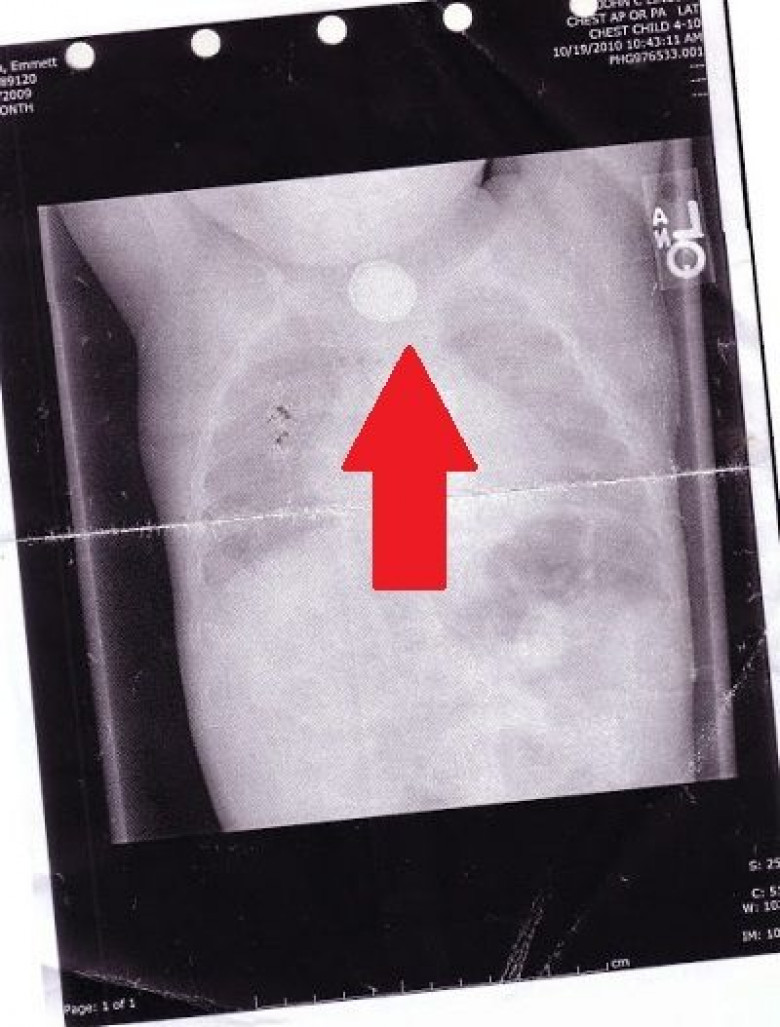

Карла и Майкл Роуч — обычная семейная пара. На фотографии супруги вместе со своими детьми, 7-летним Итаном и 5-летним Эмметом, выглядят абсолютно счастливыми. Но 4 года назад им довелось пережить настоящий кошмар. Они чуть было не потеряли маленького Эммета... Не успел малыш отпраздновать свой первый день рождения, как родители заметили, что он стал странно себя вести. Эммет был вялым и капризным и периодически кашлял. Испугавшись за здоровье сына, Карла и Майкл показали его врачу. Доктор при осмотре не выявил ничего страшного. Он решил, что это обычная простуда и назначил соответствующее лечение. Но Эммету лучше не становилось. Через несколько дней он начал кашлять кровью! Кроме того, у него началось непрекращающееся слюноотделение. Симптомы указывали на круп, но доктор решил на всякий случай направить мальчика на рентген. Снимок указал на истинную причину страданий мальчика. Оказалось, что он проглотил маленькую круглую батарейку, которую в народе называют «таблетка». Она застряла в гортани и поначалу особо не тревожила маленького Эммета. Но через некоторое время из нее потихоньку стал вытекать электролит, который начал разъедать стенки пищевода. Батарейку немедленно извлекли, но к тому времени часть щелочи уже успела из нее вытечь, нанеся мальчику огромный вред. Его гортань, пищевод и желудочно-кшечный тракт были сильно поражены электролитом. Для того чтобы вернуть малышу здоровье, ему потребовалось сделать целых 65 операций за последующие 4 года! Долгое время Эммет не мог даже самостоятельно дышать и питаться. А для того, чтобы мальчик смог разговаривать, ему пришлось сделать искусственные голосовые связки! Но, к счастью, малыш оказался настоящим бойцом. Он сумел преодолеть все невзгоды и теперь ничем не отличается от своих сверстников. Вот так обычная батарейка, которая отыщется в каждом доме, чуть не стала причиной гибели мальчика. Родители Эммета решили предупредить других людей об этой опасности, поэтому обнародовали свою историю. Так что предупреди своих знакомых о скрытой угрозе батареек — поделись с ними этой записью.